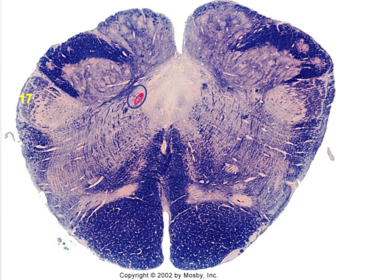

| Nucleus gracilis | |

| Accessory nucleus | |

| Medial longitudinal faciculus | |

| Pyramidal decussation | |

| Medullary pyramids | |

| Anterior spinocerebellar tract | |

| ALS | |

| Posterior spinocerebellar tract | |

| Spinal tract of V | |

| Spinal nucleus of V | |

| Nucleus cuneatus | |

| Fasciculus cuneatus | |

| Fasciculus gracilis | |

| Central canal | |